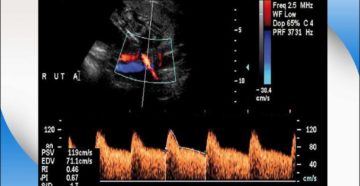

Нарушение кровотока при беременности — симптомы, лечение Нарушение кровотока при беременности встречается часто на разных…

В чем риски для ребенка при беременности нарушения маточно-плацентарного кровотока 1-а, 1-б, 2 или 3…